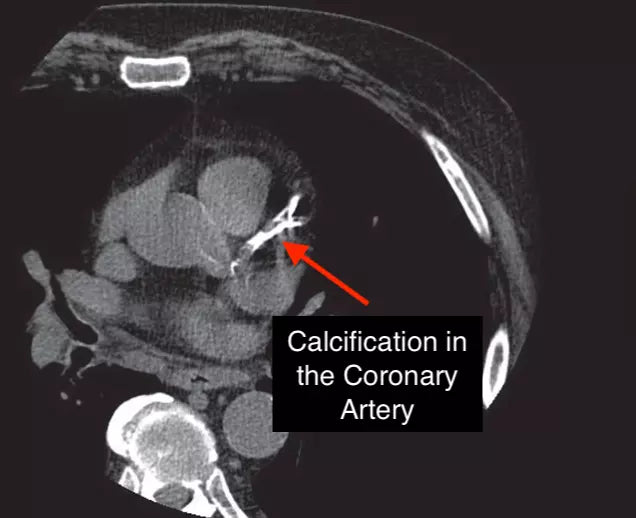

EVERYONE needs to get a CardioHealth 101! Why? Because cardiovascular Disease is the #1 cause of death of men and women. In fact, 2200 people...

Cardiovascular Disease is the #1 cause of death. However, 80% of cardiovascular disease is preventable. Here are our recommendations for how to improve cardiovascular disease and risk.